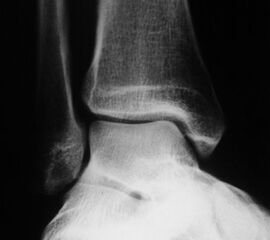

Röntgenaufnahmen dienen primär dem Ausschluss einer knöchernen Verletzung. Die Beurteilung der Geometrie der Malleolengabel kann einen ersten Hinweis auf eine Syndesmosenverletzung liefern. Die notwendigen Röntgenaufnahmen umfassen das Sprunggelenk anterior-posterior, lateral und in 20° Innenrotation (Mortise view). Zur Beurteilung der Syndesmose sind verschieden Parameter in der Mortise view beschrieben. Zu diesen zählen der tibiofibulare Clearspace, der mediale Clearspace, sowie die Überlappung der distalen Fibula und Tibia im Bereich der Incisura (Abbildung 2). Der Tibiofibulare Clearspace wird als verlässlichster Indikator für eine Syndesmosenverletzung gesehen, da er nicht signifikant von der tibialen Rotation beeinflusst wird 32. Er wird 1 cm proximal des Tibiaplafonds gemessen und sollte weniger als 6mm betragen 33. Jede Messung, die diesen Wert übersteigt, stellt einen Hinweis für eine Syndesmosenverletzung dar. Eine tibiofibulare Überlappung von 6 mm oder mehr in der AP Aufnahme, sowie mehr als 1 mm in der Mortise View Aufnahme gelten als physiologisch 33. Der mediale Clearspace sollte nicht mehr als 4 mm betragen 34.

Abbildung 3 zeigt ein Sprunggelenk nach Syndesmosenverletzung mit einem erweiterten Tibiofibularen Clearspace.